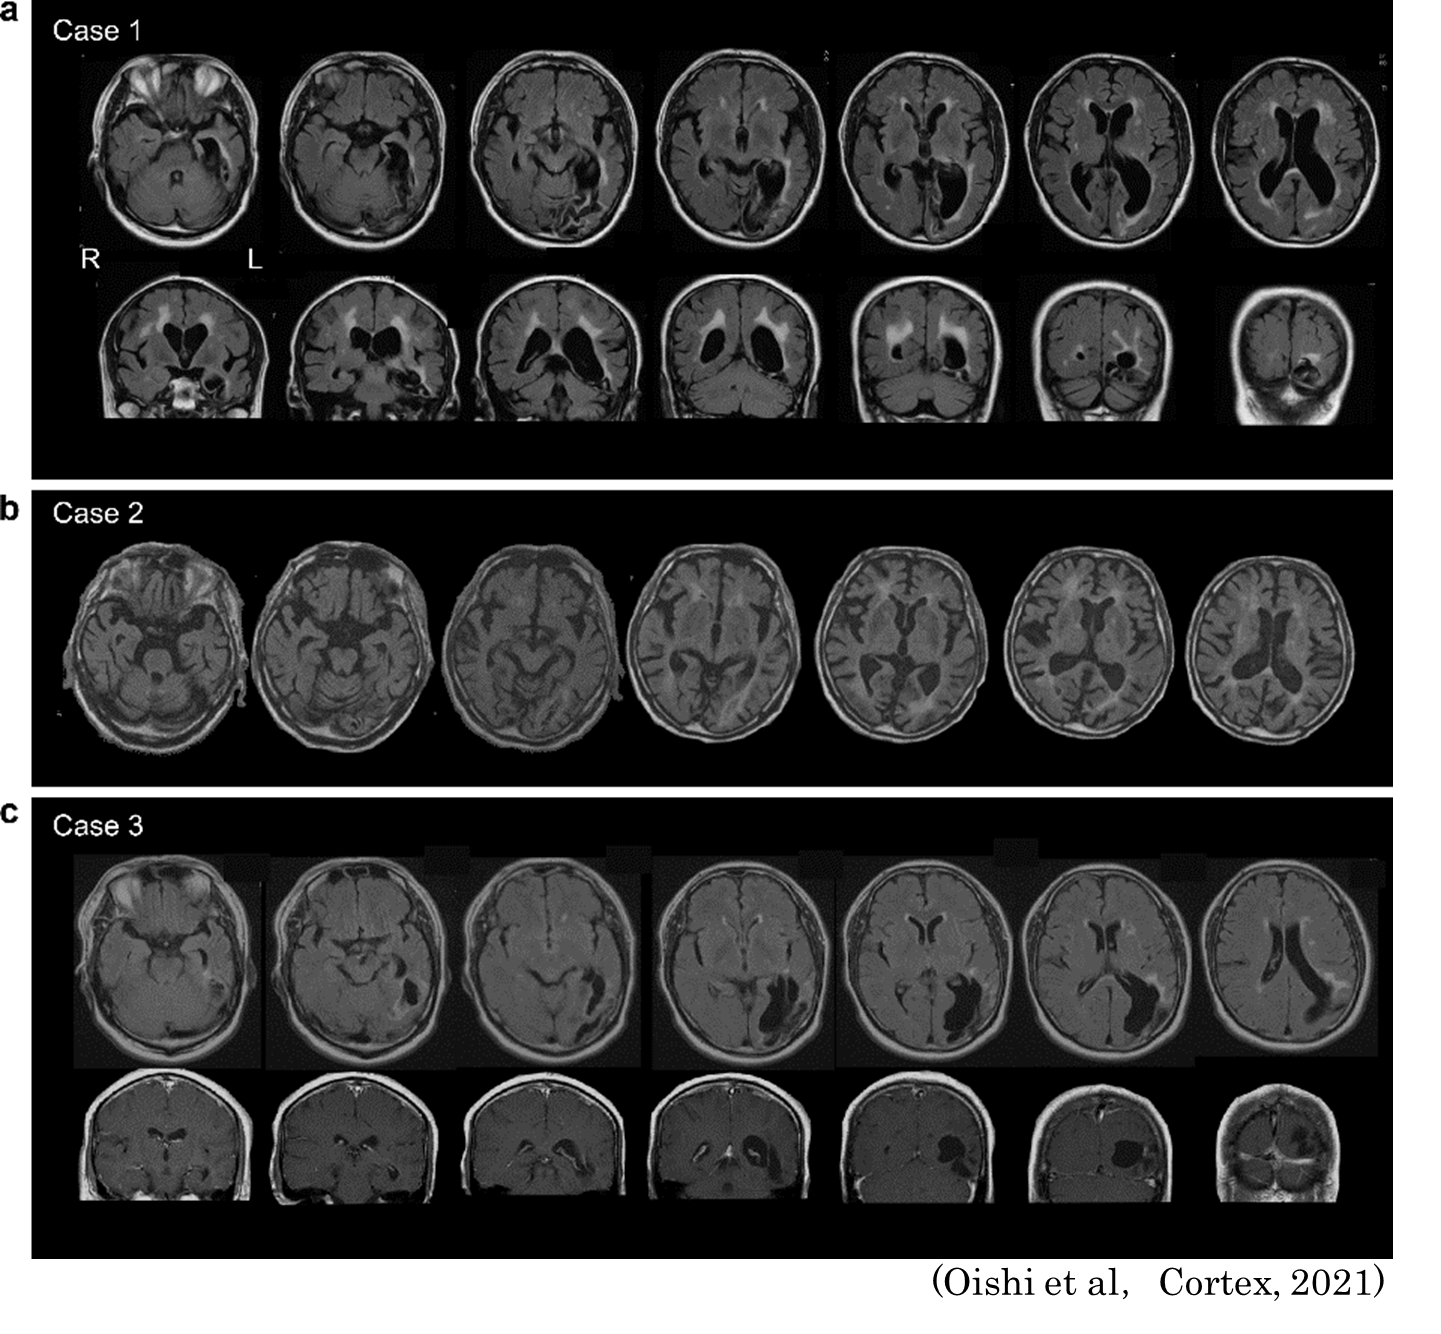

脳卒中後に左後頭葉損傷を呈した3症例における色認知障害の特徴とメカニズムについて、神経心理学的検討を行いました。

Oishi Y, Nagasawa H, Hirayama K, Suzuki K, Neural bases of color-specific semantic loss: Two cases of object-color knowledge impairment. Cortex 141: 211-223, 2021,